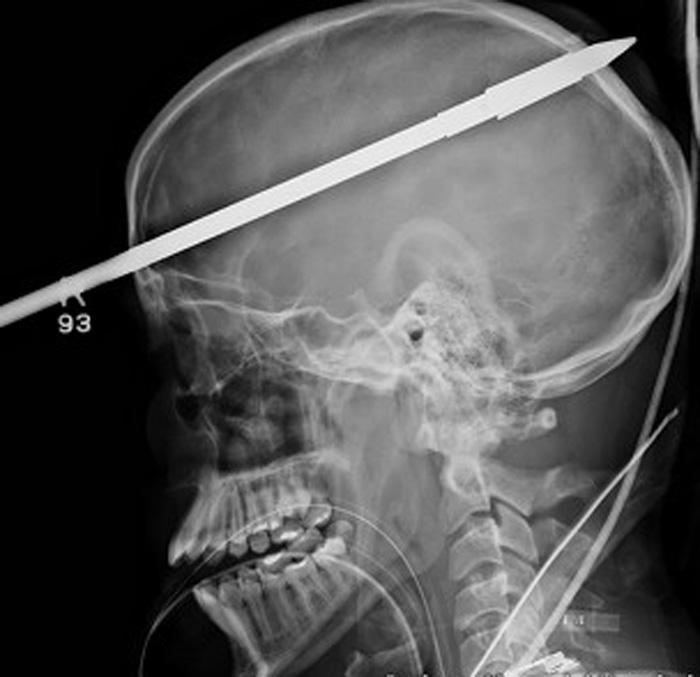

INCREIBLE. En esas condiciones llegó al hospital. FOTO TOMADA DE BBC.CO.UK

MIAMI, Estados Unidos.- Yasser López estaba pescando en Miami cuando, por error, se clavó un arpón de pesca en la cabeza que le atravesó el cerebro. Increíble pero cierto, el joven de 16 años sobrevivió al accidente y fue trasladado inmediatamente a un hospital de Miami, donde llegó consciente y tranquilo, según publica el medio inglés Daily Mail. Una vez internado, lo primero que hicieron los profesionales fue cortarle parte de la lanza para poder hacerle radiografías. La operación para extraerle la punta del arpón duró tres horas pero, afortunadamente, fue un éxito. Yasser, que tenía el arpón incrustado a la altura del ojo derecho y atravesando su cerebro, ya ha empezado a hablar y se está recuperando bien. (Especial)